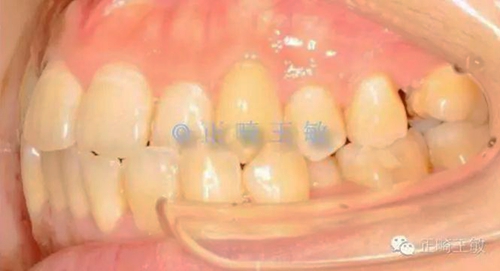

只是偏合,為了糾正,47的支抗不免喪失,最終會(huì)做成一個(gè)這樣的關(guān)系。

7.jpg

這時(shí),順理成章的種一個(gè)小一點(diǎn)的46,同樣是尖窩相對(duì),同樣的穩(wěn)定。